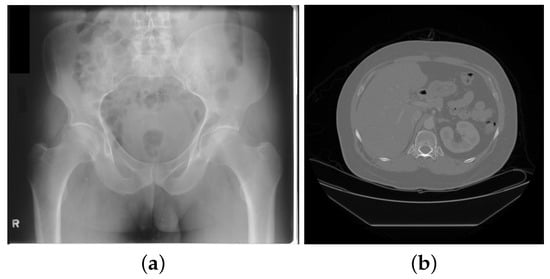

2.1. Digital Radiography and Computed Tomography

| Radiography | Chest | (2000, 2500, -, -) | 10–16 bits | 10 MB |

| CT | Abdomen | (512, 512, 500, -) | 12–16 bits | 250 MB |